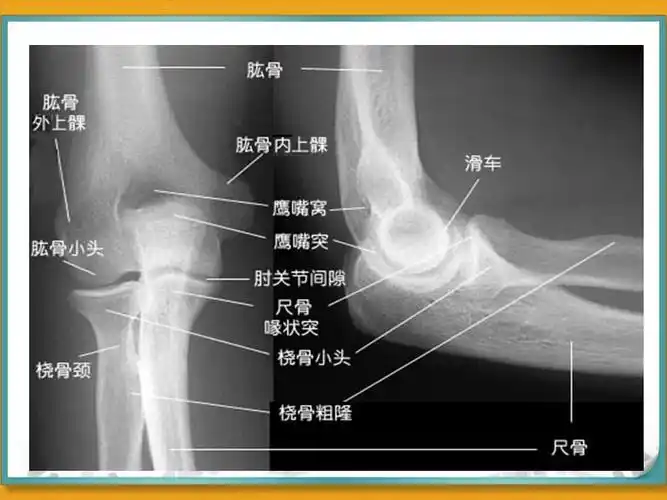

2019--8-26 肘关节x线解剖学

肘部x射线